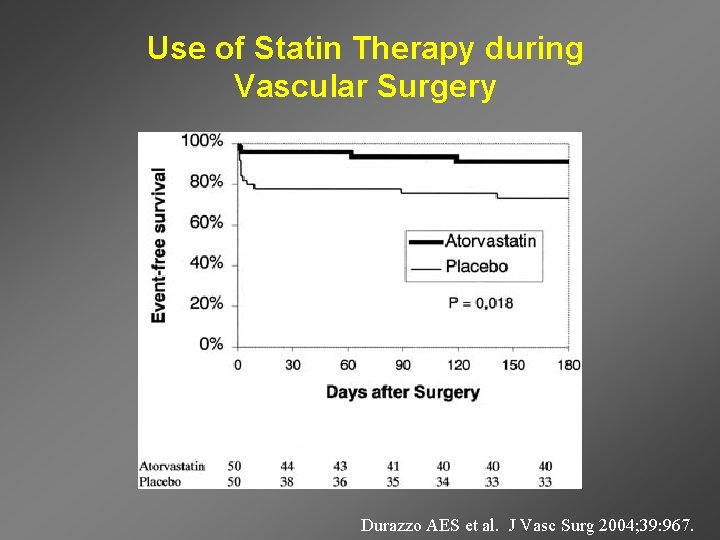

Use of Statin Therapy during Vascular Surgery Durazzo AES et al. J Vasc Surg 2004; 39: 967.